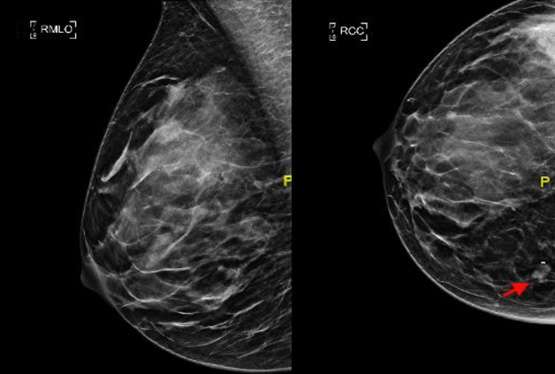

In the ideal craniocaudal view, the nipple should be positioned midline and the length of the PNL should be within 1 cm from that of the MLO view (Figure 1). The image receptor is positioned beneath the breast and compression is applied superiorly. When positioned correctly, the craniocaudal view has the advantage of showing the deep medial breast tissue which is often excluded on the mediolateral oblique view. Thus, it is imperative to ensure adequate inclusion of the deep medial breast in the CC view to detect masses that are otherwise excluded in MLO views (Figure 2).